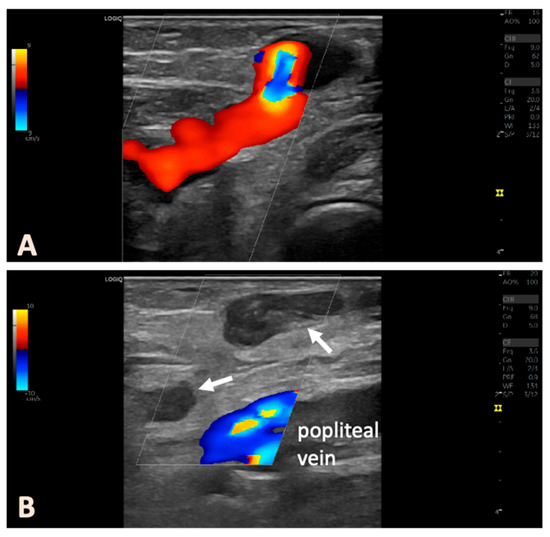

After obtaining informed consent, the surgeries were performed in a dedicated operating room under strict sterile conditions, with the patient in the prone position. Throughout the procedure, continuous ultrasound visualization was used (Logiq e, GE Healthcare, Chicago, IL, USA). Figure 1 shows an illustrative example of the treatment procedure using intraoperative ultrasound images. Conventional 16 GA venous cannulas were employed to access the targeted veins. The PFPV was punctured in such a way that the placement of the laser catheter enabled the ablation of the longest vein segment, with the catheter tip positioned as close as possible to the junction with the deep vein system. In complex cases, multiple cannulas were used, which were placed preparatively into the veins to be ablated. This step ensured secure venous access before the perivenous tumescent anesthesia was administered. After the placement of the venous cannulas, we inserted the laser catheter (1470 nm ELVeS Radial 2ring slim, Biolitec AG, Vienna, Austria) into the most proximally located venous segment. A 4 °C tumescent solution (1000 mL of physiological saline + 50 mL of 1% mepivacaine + 8 mL of 8.4% sodium bicarbonate) was then perivenously infiltrated. Particular attention was paid to creating a fluid sleeve around the treated veins to protect the surrounding tissues. The anatomical relationships with nerve structures in the popliteal fossa, including the tibial nerve, medial sural cutaneous nerve, and common peroneal nerve, were considered (Figure 1). The nerves could be well visualized in the transverse ultrasound view and, if necessary, displaced using targeted tumescent injection.

Figure 1. Representative intraoperative ultrasound images illustrating the treatment procedure using the example of a left-sided PFPV in a female patient with non-complex anatomy. (A) The transducer is positioned in a longitudinal, in-plane orientation, showing the perforating vein and its course beneath the popliteal fascia. (B) The vein is punctured with the indwelling venous cannula. (C) The hollow needle is then removed. (D) The laser fiber, visible via the slight acoustic shadow in the first cm, is positioned, and the venous catheter is withdrawn. (E) The tumescent solution is then perivenously injected. (F) The nerve structures of the popliteal fossa are only visible in the transverse orientation. Care must be taken to ensure that there is sufficient distance between the tip of the intravenous catheter and the existing nerve structures. If necessary, a targeted injection of tumescent solution is performed to increase the distance. (G,H) The laser energy is applied under continuous sonographic monitoring, even during the continuous withdrawal of the catheter.